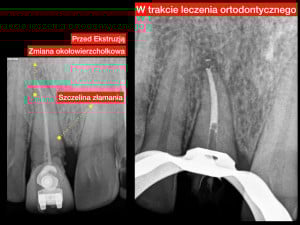

Ekstruzja ortodontyczna – wydłużenie korony klinicznej zęba. Jest ruchem wymuszonym przez siły ortodontyczne a skierowanym do płaszczyzny zwarcia, powodującym rozciąganie włókien ozębnej stymulującym jednocześnie przebudowę wyrostka zębodołowego, co daje zwiększoną objętość kości i dziąsła. Ekstruzja ortodontyczna to skuteczna metoda ratowania zębów po złamaniach koronowo-korzeniowych zębów stałych.

Głównym celem jest uratowanie zęba przed usunięciem. To metoda z wyboru w trudnych przypadkach złamań korzeni zębów przebiegających poniżej przyczepu dziąsłowego. Drugą z metod alternatywnych jest periodontologiczne-mikrochirurgiczne wydłużenie korony klinicznej.

Przykład ekstruzji ortodontycznej za pomocą płytki termoformowalnej i zameczka ortodontycznego: